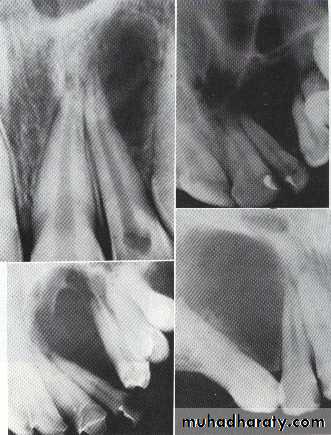

Lesions around crown of impacted tooth

Dentigerous CystIt forms around the crown of an unerupted or supernumerary tooth at CEJ.

Some dentigerous cysts are eccentric, developing from the lateral aspect of the follicle so that they occupy an area beside the crown instead of above the crown.

It displace and resorb adjacent teeth.

It commonly displaces the associated tooth

in an apical direction.

The term eruption cyst is used to describe a dentigerous cyst when it is in the soft tissues overlying the unerupted tooth.• Odontogenic Fibroma

• Benign tumor appear as a solid mass, around the crown of impacted teeth.• Odontogenic Myxoma

*They are benign, intraosseous neoplasms that arise from the mesenchymal portion of the dental papilla.

*Monolucular or multiloculor radiolucency associated with missing or unerupted tooth.

*Can be distinguished from the Fibroma by histological examination(excessive ground substance myxoid tissue).

A: Odontogenic fibroma

B,C,D:Odontogenic myxoma.Odontogenic Adenomatoid Tumor (OAT)